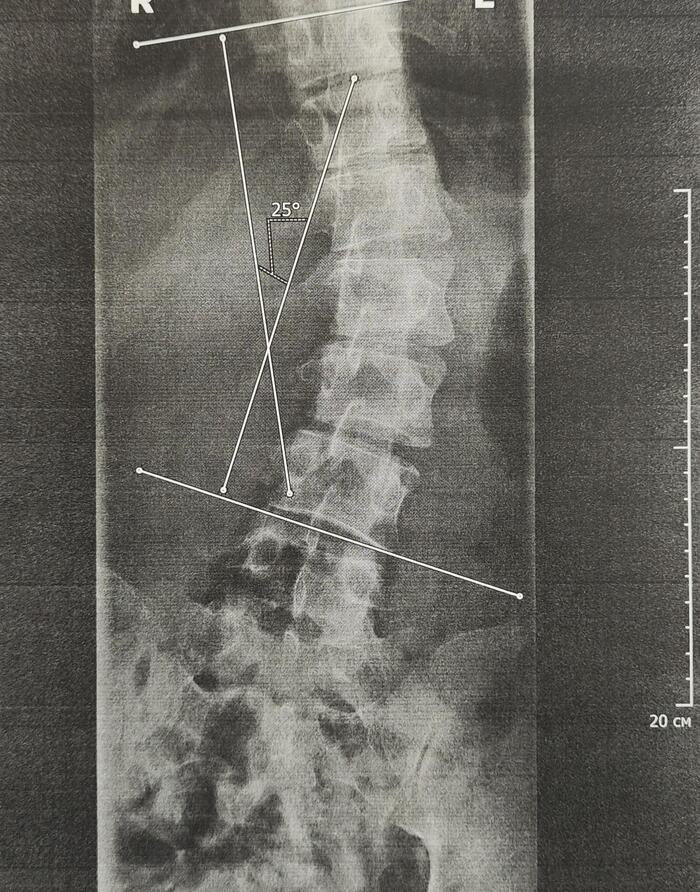

На Р-граммах грудного, поясничного отделов позвоночника определяется S -образное искривление оси позвоночника, с левосторонней дугой, вершиной на Th10,угол девиации 20 град., правосторонней дугой, вершиной на L2, углом девиации 15 град.

В данном случае непризывные категории годности будут по сколиозу 2 ст(угол искривления более 18 град.)-ст.66в-В(ограниченно годен к в/сл), гиперкифозу грудного отдела позвоночника 4 ст, с клиновидной деформацией 3х позвонков грудного отдела как следствие остеохондропатии-ст.66а-Д(не годен к в/сл),иногда ставится 66в-В.